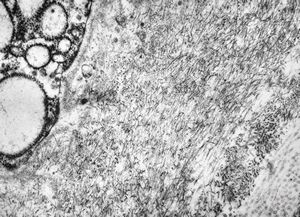

M,1y. | unusually cup-shaped mitochondria - plexus papilloma

M,1y. | intramitochondrial inclusion - plexus papilloma